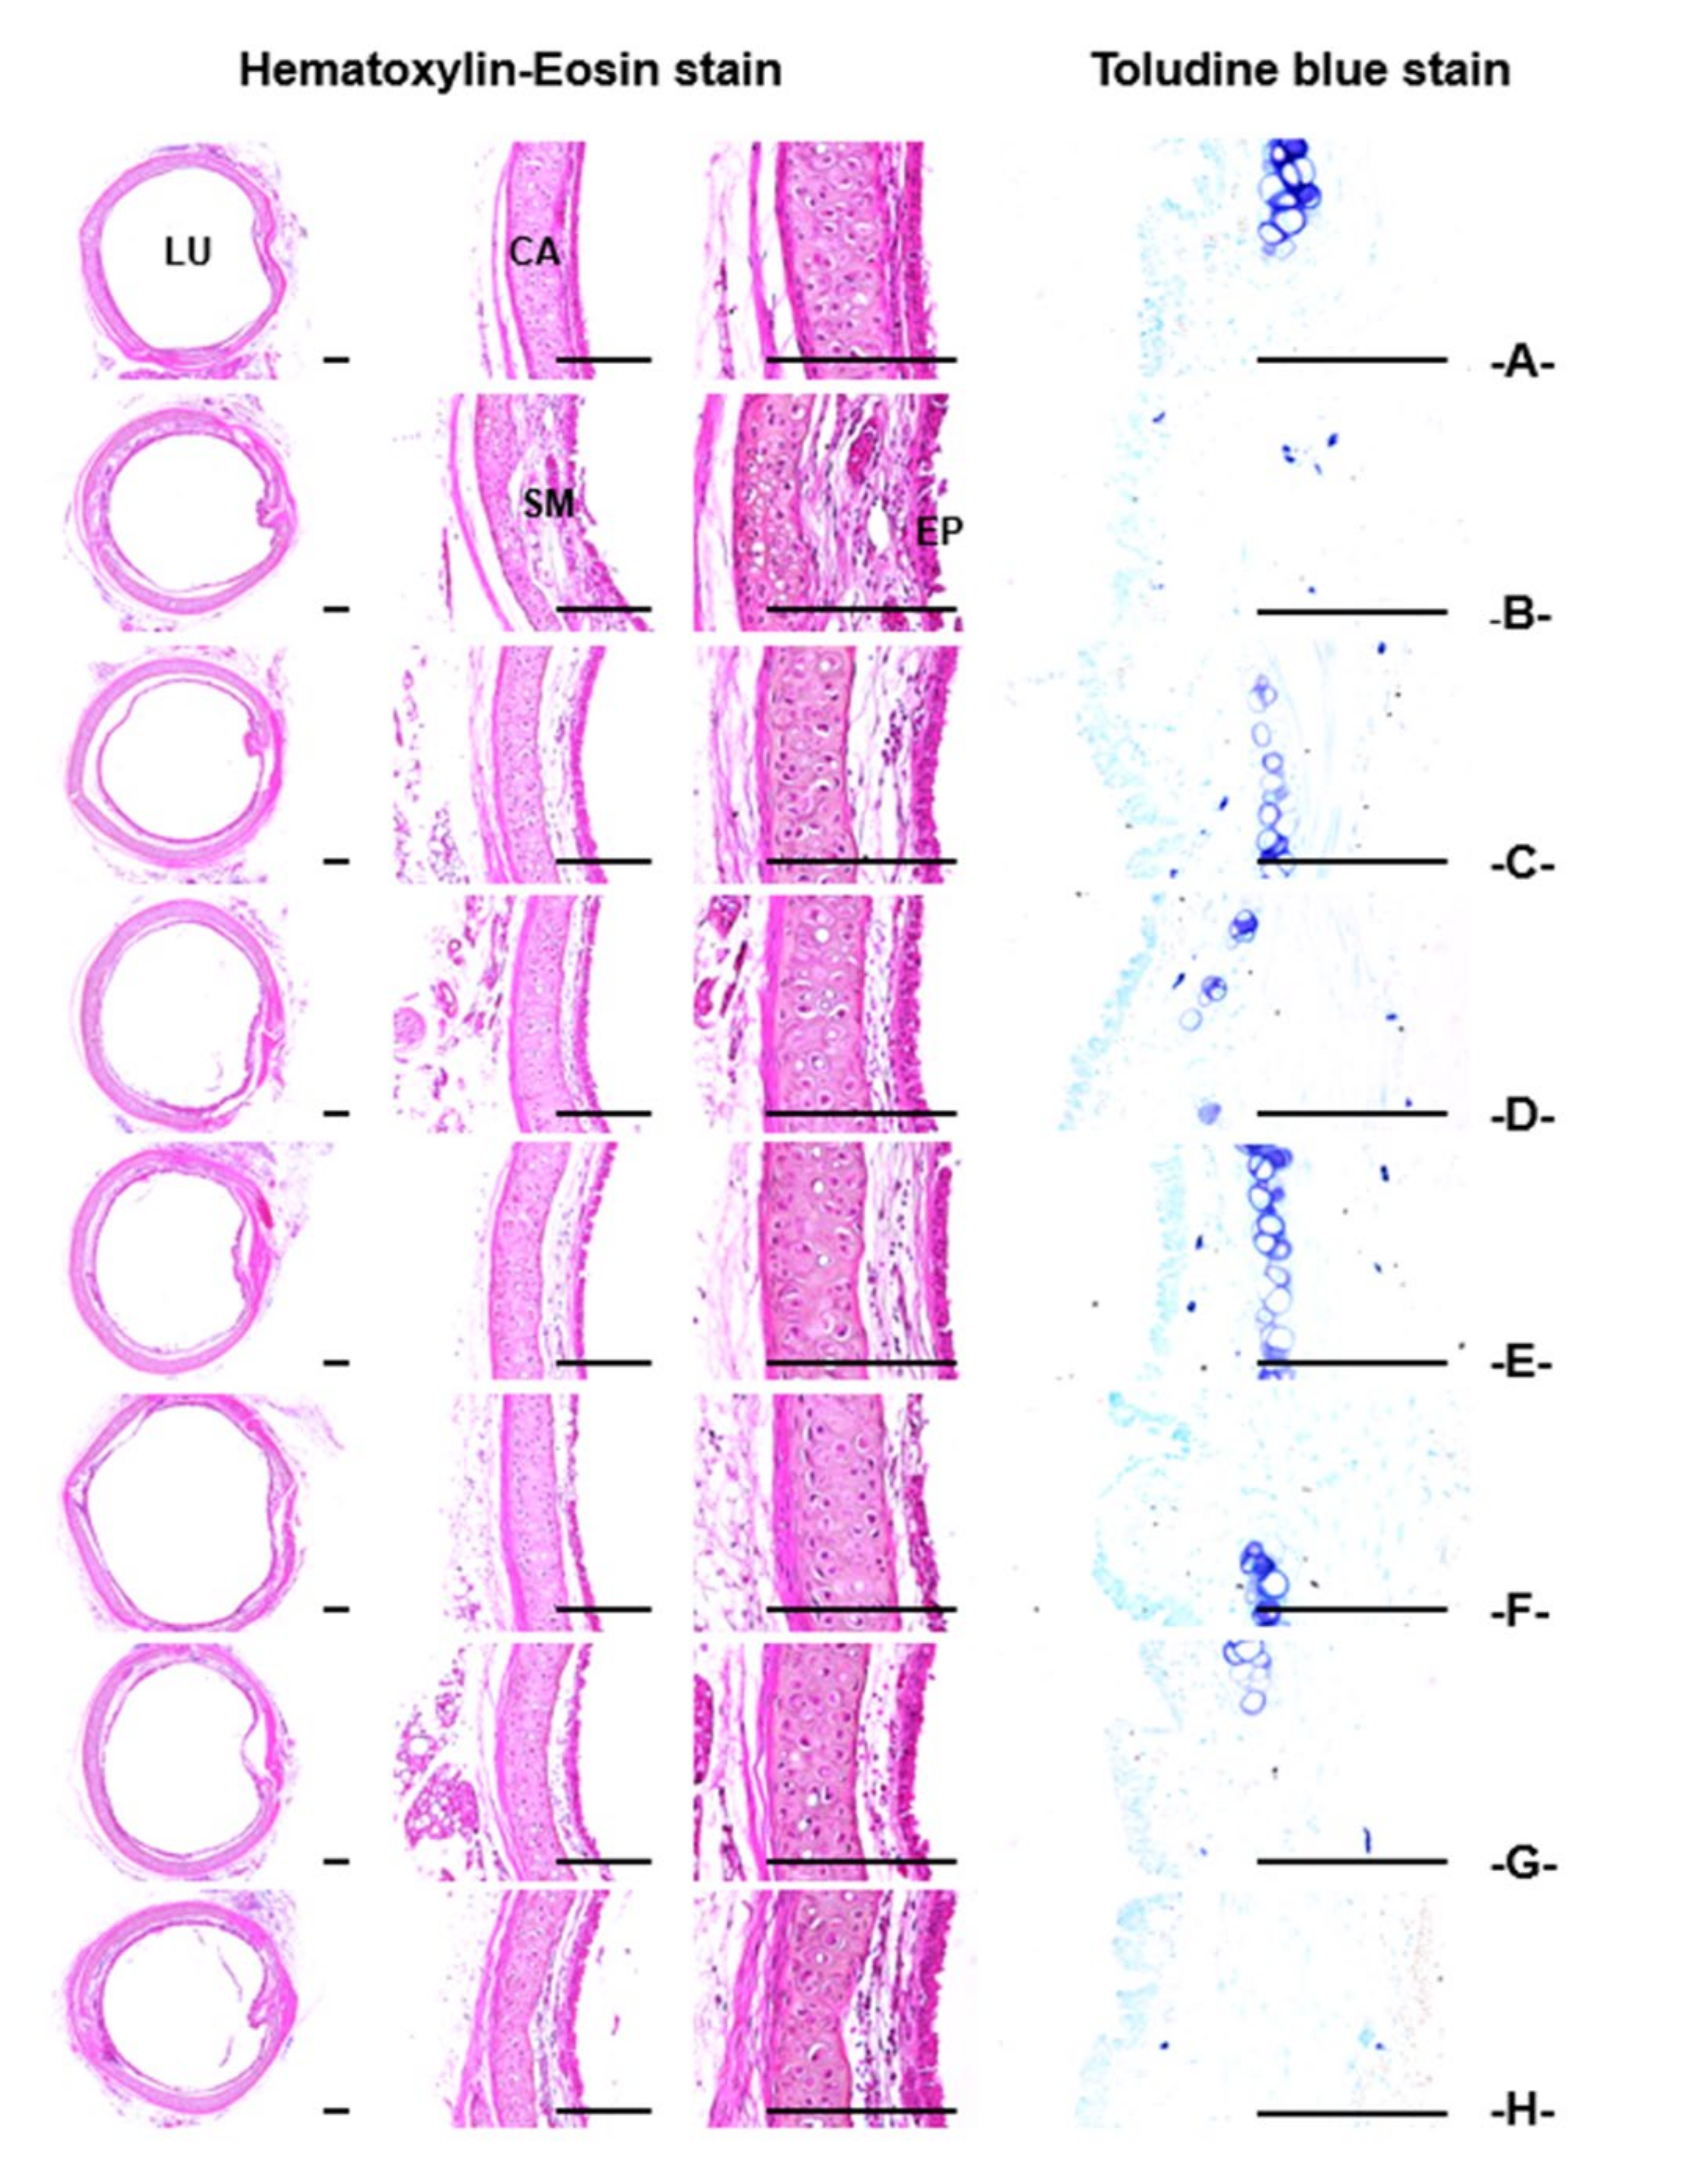

3.2.3. Histopathological Findings of the Trachea and Lung